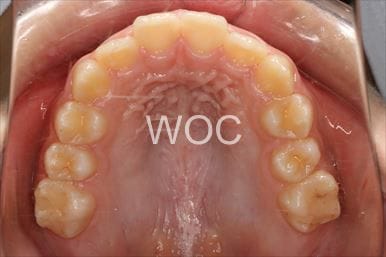

八重歯・叢生マウスピース型(カスタムメイド)矯正装置(インビザライン)

マウスピース型(カスタムメイド)矯正装置(インビザライン)を希望。ガタガタ(叢生)が強く上顎両側第一小臼歯抜歯か非抜歯のボーダーラインケースだったが、装置装着時間の協力も良く非抜歯で終了となりました。

- 年齢:35歳女性

- 主訴:ガタガタ

- 基本矯正料金:88万円

- 治療期間:2年6ヶ月

- 非抜歯

-